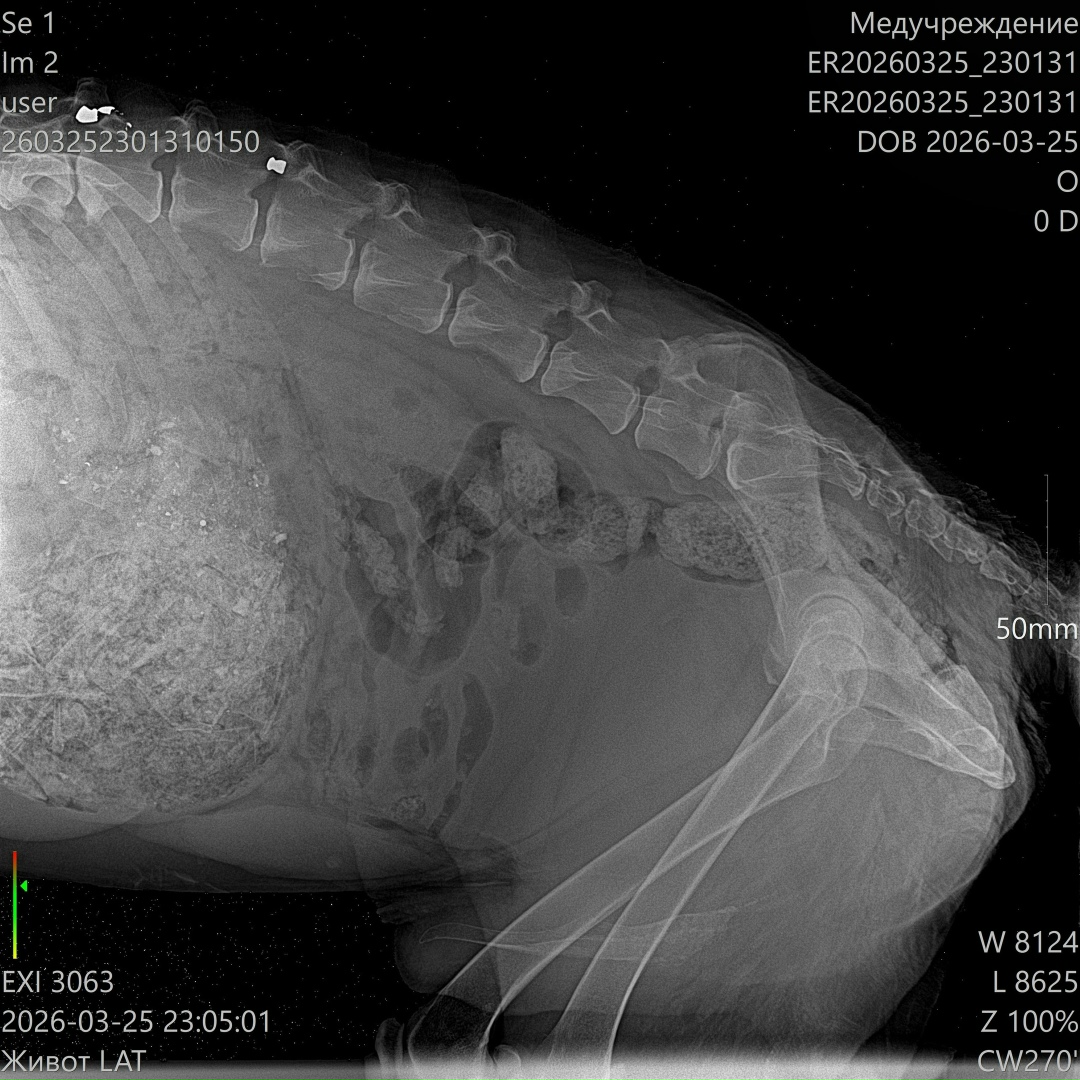

Сейчас он в клинике в тяжёлом состоянии: высокая температура, сильно повышены лейкоциты. По УЗИ свободной жидкости нет, но в желудке — куча костей… и самое страшное — пуля в позвоночнике 😭